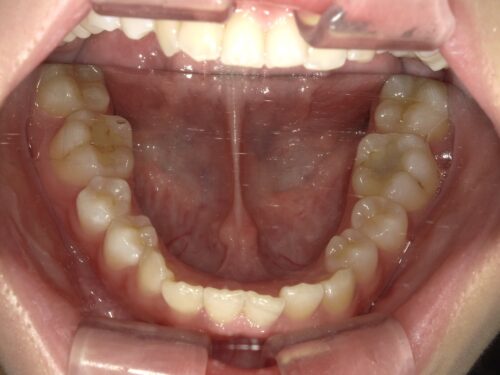

治療前・下顎の写真

下の歯並びを見ると、前歯にがたつき(叢生)があるのが確認できます。歯が重なり合って並んでいる状態ですね。